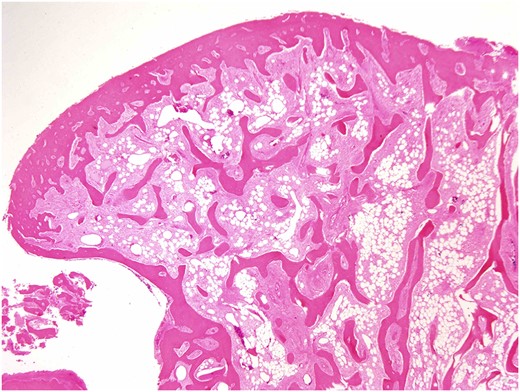

Both specimens showed identical histopathological features, being composed of chronically inflamed nasal mucosa undermined and compressed by sharply demarcated, zonated, multilobulated osseous proliferation without any cartilaginous component. The core and bulk of the lesions was composed of anastomosing, cancellous type bony trabeculae separated by fibrofatty marrow spaces, surfaced by denser cortical type bone, features characteristic of benign osteoma (Figs 2 and 3).

Osteoma, high-magnification photomicrograph. Scanning power photomicrograph showing disrupted pieces of multilobulated variably hyperostotic bone characterized by central anastomosing cancellous trabeculae and fibro-adipocytic interstices, surmounted by more sclerotic cortical type bone. Note the complete absence of any chondroid element (H&E stain, original magnification ×1).